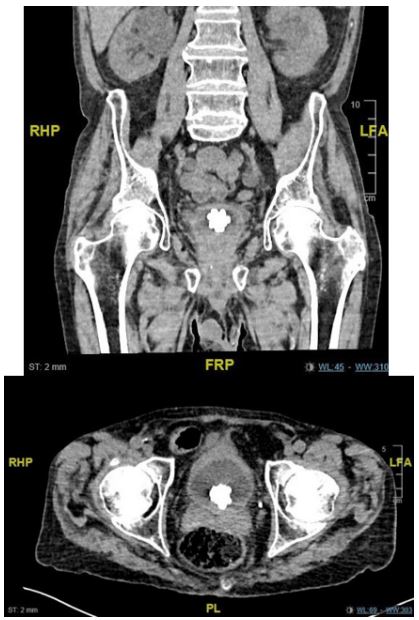

A 73- years-old man was referred to emergency department with bilateral flank pain and new-onset hematuria. He had a history of prostatic cancer and recurrent urinary tract infections. On physical examination, there was tenderness and an enlarged lower abdomen over the suprapubic region. Insertion of urinary catheter reviles of urinary retention with more than 1000 CC of urine and urinalysis showed hematuria and pyuria. A subsequent abdominal CT showed a unique jackstone calculi in pelvic region-named after a toy jack- typically form in the bladder because of urine stasis and are usually composed of calcium oxalate dihydrate.

Figure 1: